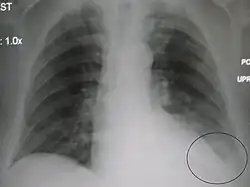

AP CXR showing pneumonia of the lingula of the left lung -